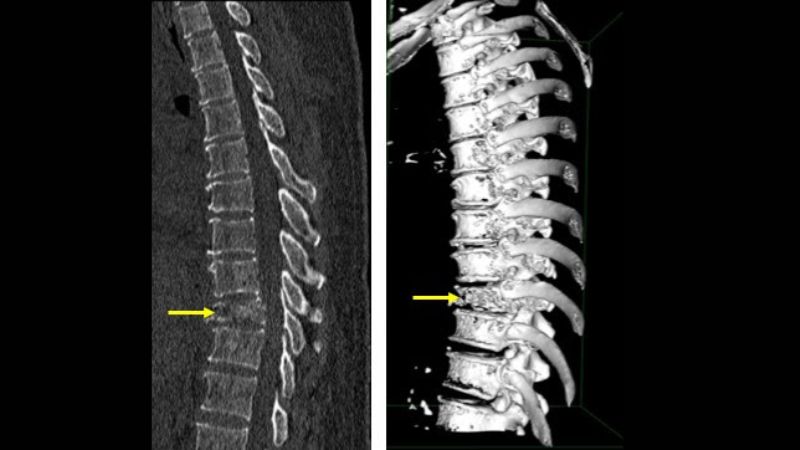

- Gai cột sống: Canxi là khoáng chất cần thiết giúp xương chắc khỏe. Tuy nhiên, khi canxi lắng đọng quá nhiều ở cột sống, các gai xương nhỏ có thể hình thành. Những mỏm gai này chèn ép vào rễ thần kinh, khiến người bệnh cảm thấy đau và tê lan dọc cột sống.

- Lao cột sống: Lao cột sống (còn gọi là mục xương sống) là bệnh lý do vi khuẩn lao xâm nhập vào cột sống qua đường máu hoặc hệ bạch huyết. Bệnh khiến các đốt sống bị tổn thương, biến dạng và gây chèn ép rễ thần kinh, dẫn đến đau nhức kéo dài.